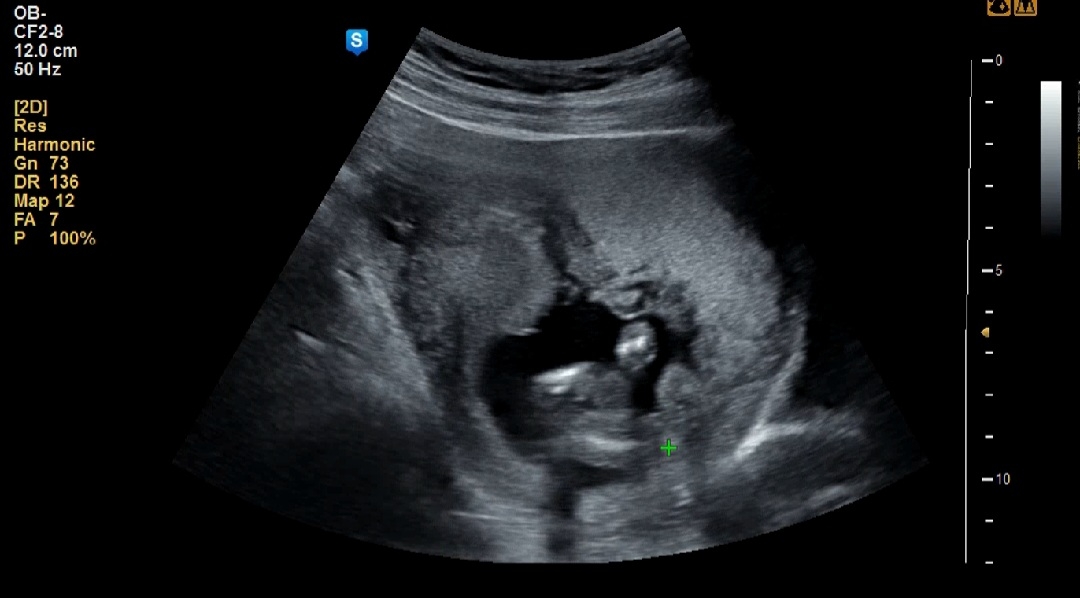

아들

의사쌤이 저부분 뭐가 보인다고 아들같다고하셨능데 저는 뭔지 모르겠어요ㅠㅜ 초음파 넘 어려워요... 보이시는분